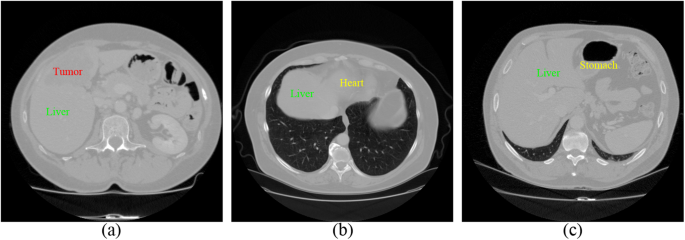

Fully Automatic Liver Segmentation Combining Multi Dimensional Graph Cut With Shape Information In 3d Ct Images Scientific Reports